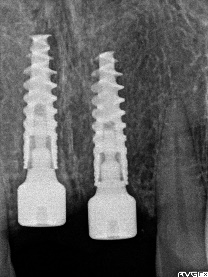

レントゲンで詳しく診てみると、虫歯が歯根のほうまで進行し、保存することができないことがわかり、抜歯しました。抜歯後、骨が大きく欠損していましたので、骨造成を行いインプラントを2本埋入しました。

抜歯後の欠損したところを補う方法には、部分入れ歯、ブリッジ、インプラントがあることを説明したところ、自分の歯と同じような感覚で嚙むことができるインプラントを選択されました。この方は、2016年に右下にインプラント治療をし、インプラントの良さを十分に理解しておられましたので、今回も2本歯を失ったところにインプラント治療を希望されました。今回もX-Guideを使った埋入で、安心安全に行うことできました。

インプラント2本:¥363,000×2本=¥726,000(税込)

骨造成:¥55,000(税込)

合計:¥781,000(税込)